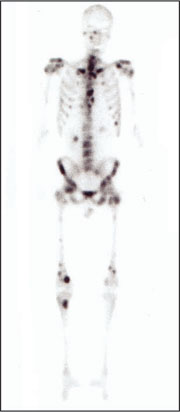

Im menschlichen Skelett wird ständig Kalziumphosphat aus- und eingebaut. Diese Umbauprozesse finden dort besonders intensiv statt, wo der Knochen stark beansprucht wird oder aber in erkrankten Knochen- und Gelenkregionen. Mit Hilfe der Skelettszintigraphie (Tc-99m-Phosphonate) lässt sich dieser Phosphatstoffwechsel sichtbar machen. Damit ist es möglich, anhand von Stoffwechselveränderungen Erkrankungen des Skeletts nachzuweisen, lange bevor morphologische Veränderungen am Knochen auftreten. Dies spielt zum Beispiel bei Krebspatienten eine Rolle, deren Tumor möglicherweise bereits Tochtergeschwülste in das Skelett abgesiedelt hat (insbesondere bei Brust- und Prostatakrebs). Weiterhin lassen sich mit Hilfe der Skelettszintigraphie Entzündungen des Knochens oder der Gelenke nachweisen. Das Szintigramm zeigt nicht nur Lage und Intensität des oder der Entzündungsherde(s), sondern es ermöglicht auch die Differenzierung zwischen Knochen- und Weichteilentzündung. Da mit nur einer Untersuchung das gesamte Skelett abgebildet werden kann, lassen sich ohne zusätzliche Strahlenexposition weit entfernte Krebsmetastasen ebenso aufspüren wie verstreut liegende Entzündungsherde. |

links: normales, also gesundes Skelettszintigramm; rechts: Skelettszintigramm mit zahlreichen Metastasen, also Tochtergeschwülsten eines Krebstumors. |